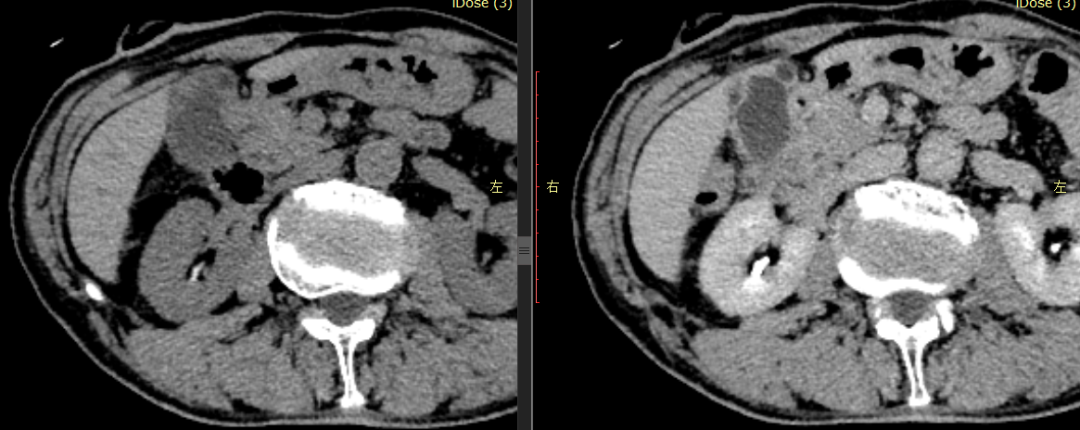

CASE 4